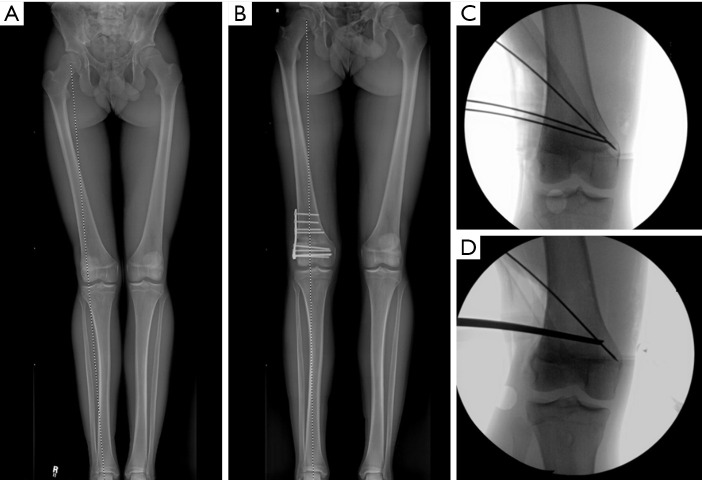

膝关节周围截骨术是一种有效的方法,通过纠正膝关节的整体排列来保护膝关节。虽然截骨术历来被用于治疗膝关节病理,但最近作为一种治疗策略重新引起了人们的兴趣,这种治疗策略可用于矫正关节位、韧带稳定和软骨保护。截骨术是纠正矢状面和冠状面排列的一种有效方法,可以保存和/或保护膝关节内侧、外侧和髌股间室的软骨,并改善膝关节韧带的稳定性。内侧开口楔形高胫骨截骨术(MOW-HTO)和外侧闭合楔形高胫骨截骨术(LCW-HTO)是矫正内翻畸形的常用截骨术,各有不同的适应症、手术技术和相关并发症。同样,股骨远端截骨术(DFO)在矫正内翻和外翻错位中起着至关重要的作用,在单独胫骨截骨术会导致关节线倾斜度过高(JLO)的情况下可能尤为重要。在单节段截骨不能提供最佳矫正的复杂情况下,可能需要双节段截骨来实现适当的机械轴修复,同时保持关节一致性。除了冠状面矫正外,矢状面截骨术越来越受到关注,以治疗韧带不稳定,特别是前后交叉韧带(PCL)缺陷。通过前闭合楔形或前开放楔形高位胫骨截骨术改变胫骨后斜率(PTS)可以改善前交叉韧带(ACL)和pcl缺陷患者的膝关节生物力学和稳定性。此外,胫骨结节截骨术(TTO)已成为一种重要的手术辅助治疗髌骨股骨错位和软骨保存策略。膝关节截骨术的目的是卸载受影响的腔室,保存和保护软骨和半月板,增强韧带的稳定性,从而推迟关节置换术的需要。因此,截骨术对于年轻和活跃的患者来说是一种有趣的手术。最近,随着对膝关节截骨术的重新关注,研究表明,截骨术在肢体对齐和软骨保护治疗中继续发挥关键作用。

Osteotomies around the knee are an effective method for preserving the knee joint by correcting overall alignment. Although osteotomies have historically been used in treatment of knee pathology, they have recently regained a renewed interest as a treatment strategy for alignment correction, ligamentous stability, and cartilage preservation. Osteotomies are a powerful way to correct alignment in both the sagittal and coronal plane to preserve and/or protect the cartilage in the medial, lateral, and patellofemoral compartments of the knee and improve the ligamentous stability of the knee. Medial opening wedge high tibial osteotomy (MOW-HTO) and lateral closing wedge high tibial osteotomy (LCW-HTO) are commonly performed osteotomies for correcting varus malalignment, each with distinct indications, surgical techniques, and associated complications. Similarly, distal femoral osteotomy (DFO) plays a critical role in the correction of both varus and valgus malalignment, and may be particularly important in cases where a tibial osteotomy alone would lead to excessive joint line obliquity (JLO). In complex cases where single-level osteotomy does not provide optimal correction, double-level osteotomy may be necessary to achieve appropriate mechanical axis restoration while maintaining joint congruence. Beyond coronal plane corrections, increasing attention has been given to sagittal plane osteotomies for managing ligamentous instability, particularly anterior and posterior cruciate ligament (PCL) deficiencies. Modifying the posterior tibial slope (PTS) through anterior closing wedge or anterior opening wedge high tibial osteotomy can improve knee biomechanics and stability in both anterior cruciate ligament (ACL) and PCL-deficient patients. Additionally, tibial tubercle osteotomies (TTO) have emerged as an important surgical adjunct in the treatment of patellofemoral malalignment and cartilage preservation strategies. The goal of knee osteotomies is to offload the affected compartment, preserve and protect cartilage and menisci, and enhance ligamentous stability, thereby delaying the need for arthroplasty. Therefore, osteotomies represent an intriguing procedure for young and active patients. Recently, with the renewed interest in osteotomy procedures about the knee, studies have demonstrated that osteotomies continue to play a critical role in treatments for limb alignment and cartilage protection.